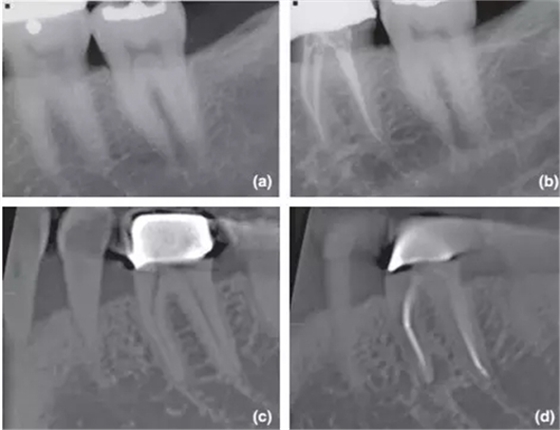

36術(shù)前X片,無根尖暗影;

1年回訪X片,根尖周無異常,診斷為成功的根管治療;

CBCT對同一個(gè)36進(jìn)行術(shù)前掃描,無根尖暗影;

1年回訪使用CBCT,發(fā)現(xiàn)新出現(xiàn)的根尖暗影,診斷為和X片完全相反的根管治療失敗。

CBCT掃描不受解剖噪點(diǎn)影響,對根尖周組織還原度高,而且還能做出精確的線性和容積測量,這些特點(diǎn)都十分有利于對骨損愈合的監(jiān)控。其中最具影響力的文獻(xiàn)當(dāng)屬由 Patel 在2012年發(fā)表的根管治療術(shù)后1年回訪臨床實(shí)驗(yàn),是第一篇應(yīng)用CBCT進(jìn)行術(shù)前及術(shù)后后掃描比較的研究。